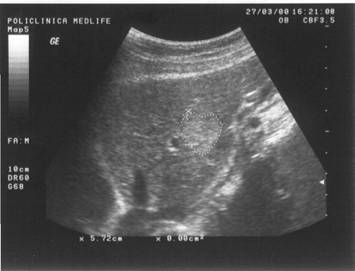

Figura 1. Vezica urinara

Figura 2. Chist renal stang situat in treimea medie

Figura 3. Chist ovar drept

Figura 4. Chist hepatic